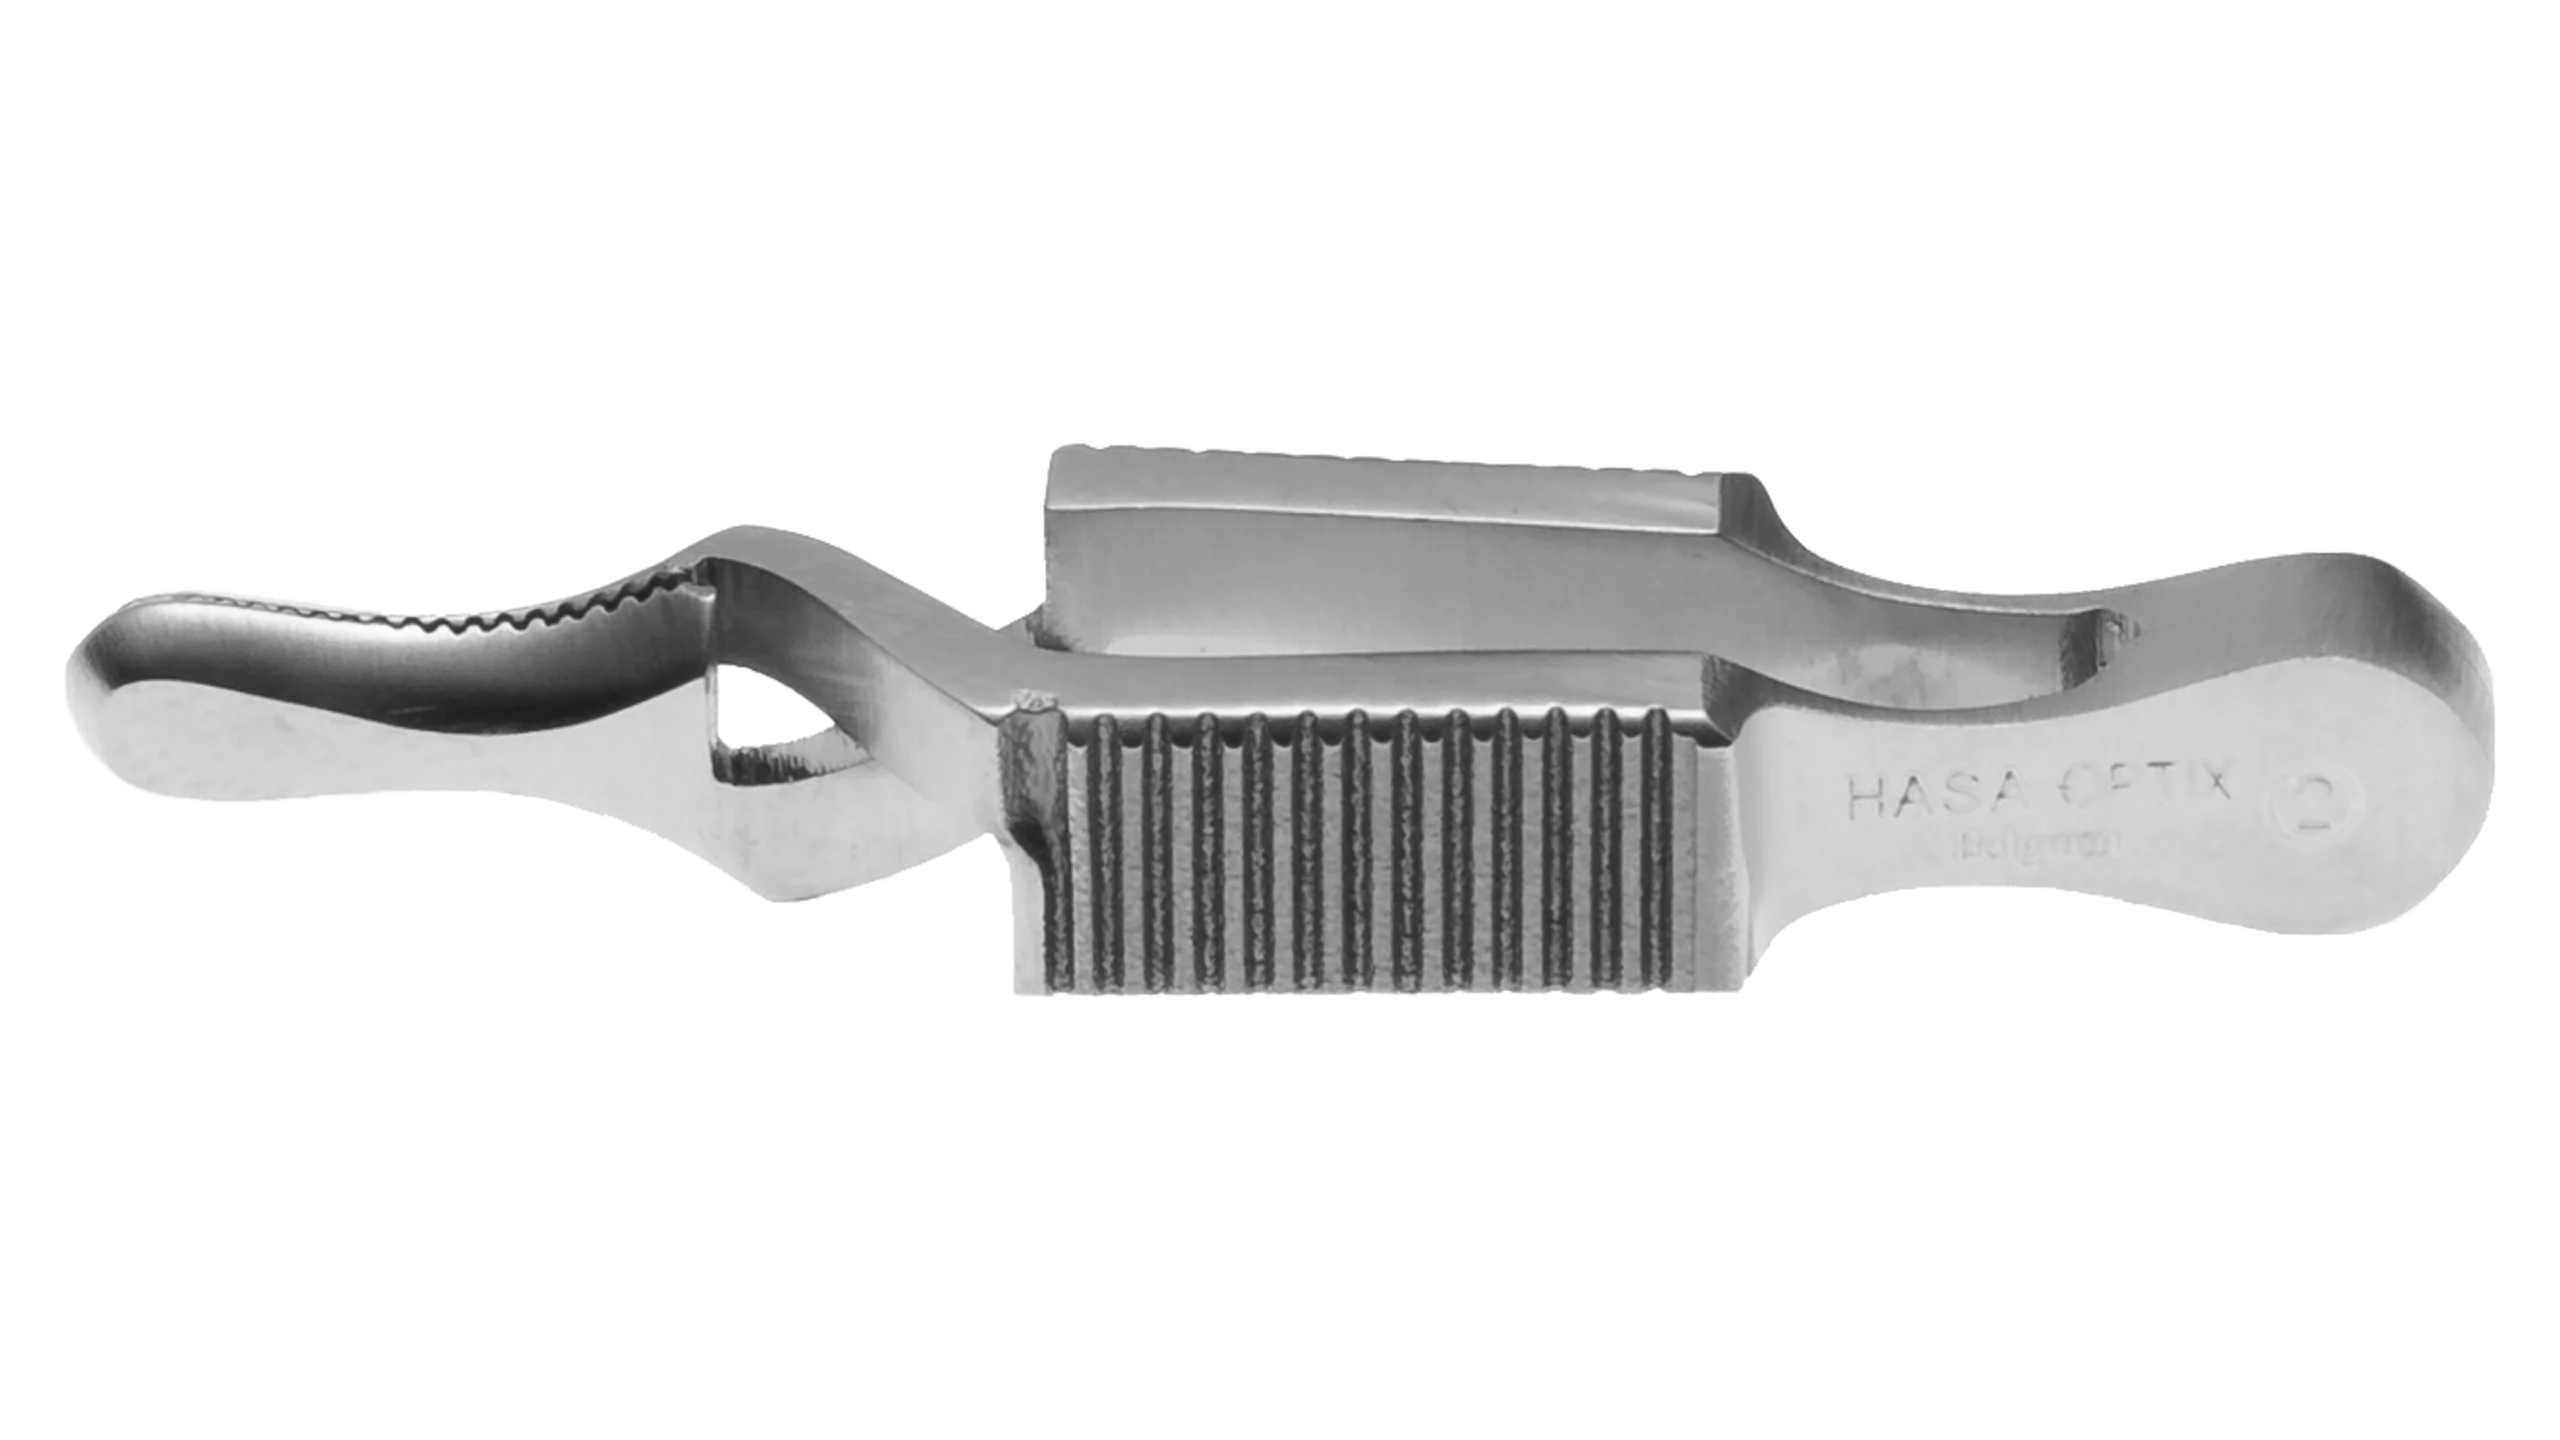

Ophthalmic Surgical Instruments

Wide range of recyclable ophthalmic surgery instruments.